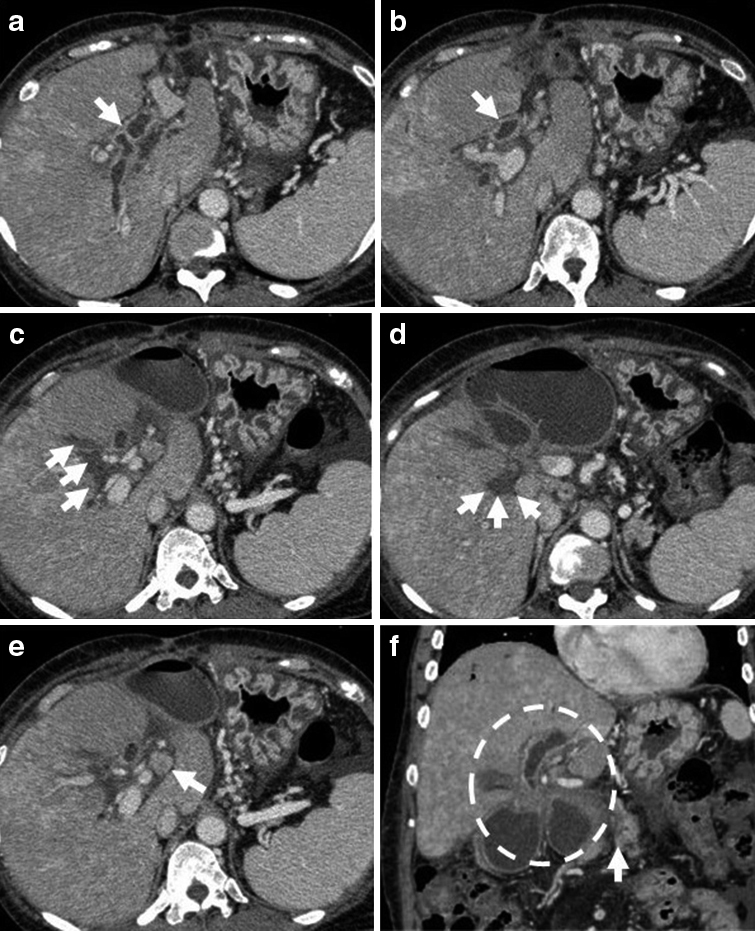

経過:繰り返す胆管炎の臨床的経過,および腹部造影CTでの挙上空腸の囊状拡張の所見から,挙上空腸に何らかの通過障害が疑われたため,ERCPを施行した.胆管空腸吻合部近傍の挙上空腸に狭窄を認めたものの,胆管空腸吻合部まで内視鏡は到達可能であった.胆管空腸吻合部には明らかな狭窄は認めなかったが,胆管空腸吻合部より盲端側の挙上空腸は著明に拡張し,腸管内に腸石,および胆石を認めた(Fig. 2a).以上より,挙上空腸の狭窄に伴う急性胆管炎の可能性を考え,挙上空腸内に内視鏡的胆道ドレナージ(endoscopic nasobiliary drainage;ENBD)用の6Frチューブを留置し,その後速やかに胆管炎は軽快した(Fig. 2b).しかし,ステント挿入1週間後にステント閉塞による急性胆管炎が再燃したため囊状拡張した挙上空腸を経皮的に穿刺ドレナージを行った.この時のドレーン造影では,拡張した挙上空腸内から肛門側腸管内への造影剤の排出は認められなかった(Fig. 3).ERCP施行時,胆管空腸吻合部から左右肝管二次分枝まで広範囲にわたって胆管上皮にびまん性の大小不同の顆粒状粘膜を認めており(Fig. 2c),さらに入院時の腹部造影CTを見直すと,挙上空腸の狭窄部は肝門部に集束するようにひきつれ,狭窄しており,癌による浸潤と考えた.また,肝十二指腸間膜内には腫大したリンパ節を認めた(Fig. 4a~f).左右肝管,および肝門部胆管上皮から生検を施行したところ,病理学的検査にて腺癌と診断された(Fig. 5a~c).以上より,切除不能肝門部胆管癌,T4aN1M0 stage IVAと診断した.

a) Choledocho-jejunostomy was indicated by the white arrow in contrast enhanced CT, and the wall thickness of the hepatic duct was shown with contrast enhancement. b) The undilated jejunal limb was demonstrated by the white arrow. c-d) Soft tissue infiltration was widespread. e) A lymph node of the hilus hepatis was enlarged. f) The jejunal limb was involved in the soft tissue mass and was dilated. White arrow indicating the pancreatico-jejunostomy.